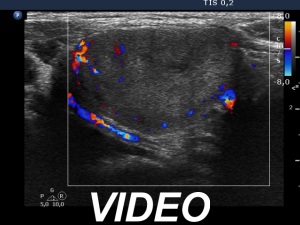

Ultrasonography. The thyroid was echonormal. There were two nodules in the left lobe. The upper, minimally-moderately hypoechoic showed taller-than-wide sign and had two microcalcifications. The lower nodule was a dominantly echonormal lesion. This showed an incomplete halo and signs of perinodular blood flow. The volume of the nodules has not been changed since their recognition.